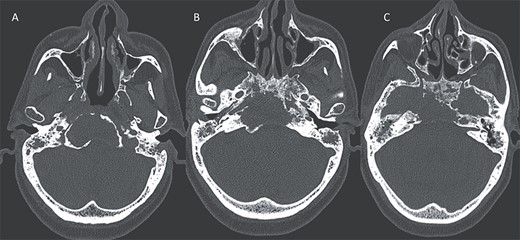

A computed tomography (CT) scan with intravenous contrast was performed (Figs 1 and 2), it revealed:

Bone destruction extending to the petrous, tympanic, and mastoid portions of the temporal bone, with involvement of the body and right greater wing of the sphenoid as well as the occipital bone, and concomitant sequestrum formations within the necrotic bones.

Presence of soft tissue in the middle ear cavity and in the mastoid cells.

Axial CT in bony window showing: (A, B) extensive bone erosion of the clivus and the body and right greater wing of the sphenoid. (C) Soft tissue in the middle ear cavity and mastoid cells.